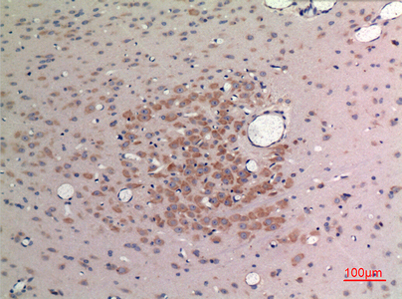

Product name: FGF-9 rabbit pAb

Dilutions: Western Blot: 1/500 - 1/2000. IHC-p: 1:100-300 ELISA: 1/20000. Not yet tested in other applications.

Immunogen: The antiserum was produced against synthesized peptide derived from the C-terminal region of human FGF9. AA range:141-190